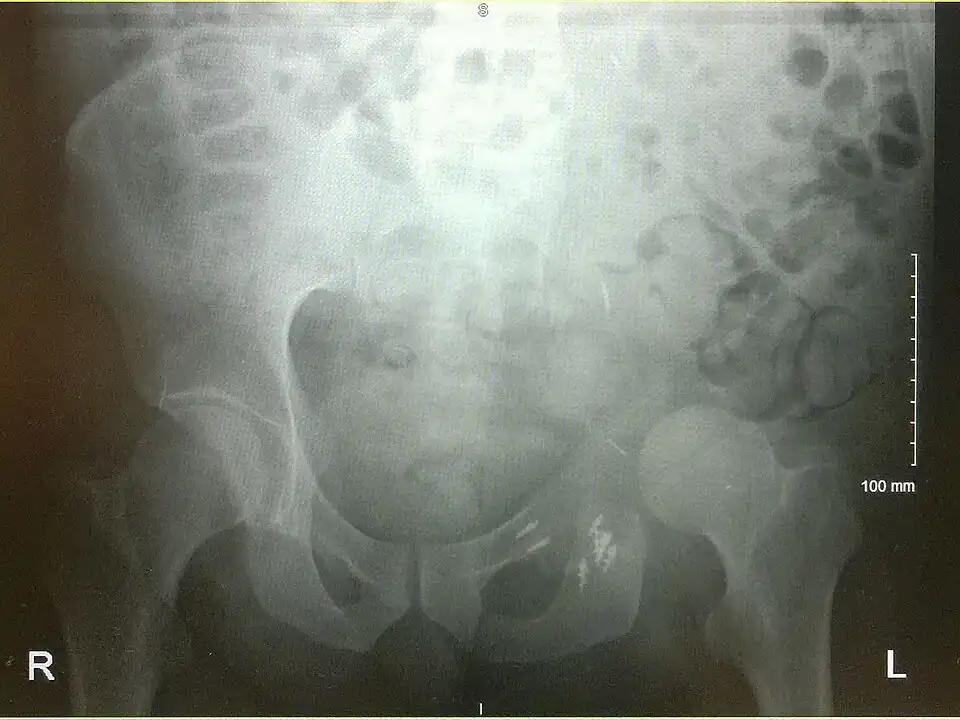

An x-ray of a limb-sparing hemipelvectomy on the left side of a male pelvis taken one month after surgery. -